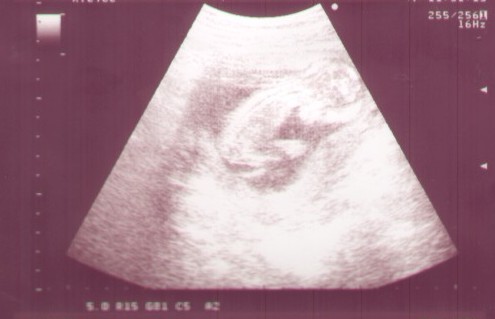

a to moje usg kontrolne, z niedzieli. Skanowane i jakoś słabo przez to wyszło, ale myślę że dzidziusia bedzie widać jak sie powiększy fotkę :-)

Teraz ma 76 mm i jest młodszy z usg o 5 dni niż z OM.

Najbardziej podoba mi się pierwsze, tak fajnie kręgosłupek widać:) duży buziak w brzusio